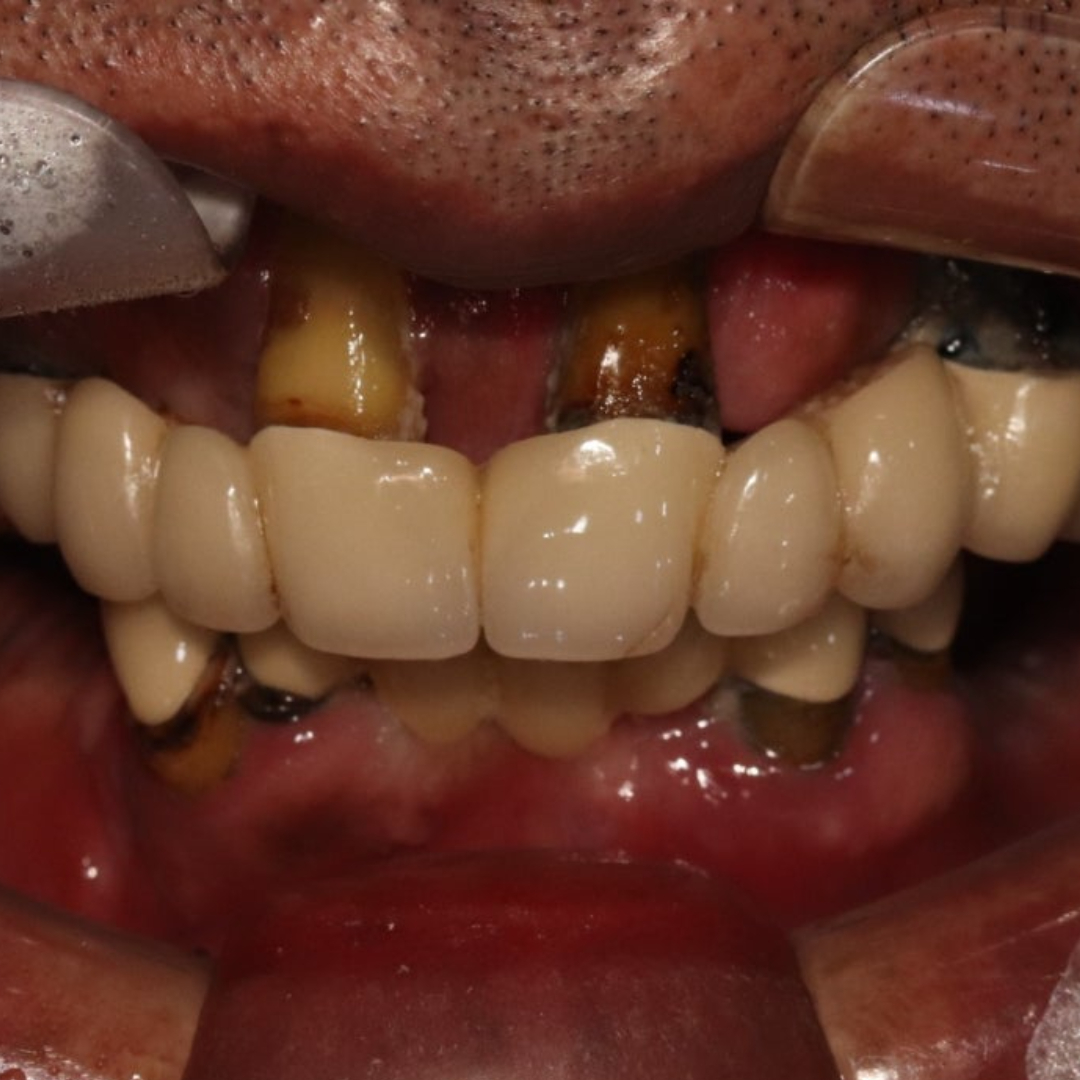

• 본 컬럼은 56조 제 1항의 의료법을 준수하여 작성되었으며 실제 내원 환자분의 동의하에 공개된 치료과정의 사진이 포함되어 있습니다.

개인에 따라 진료 및 치료방법이 다르게 적용될 수 있으며, 효과와 부작용이 다르게 나타날수 있는점을 안내 드립니다.